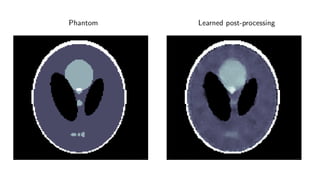

Results

ellipses

Results for ray transform inversion in 2D.

Inverse problem:

g = P(f ) + δg

Geometry: Parallel beam, sparse view (30 angles)

Noise: 5% additive Gaussian

Data: 128 × 128 pixel ellipses

Compare to:

Post-processing deep learning by U-Net

Phantom Learned post-processing

Quantitative

Method PSNR (dB) SSIM Runtime (ms) Parameters

FBP 19.75 0.597 4 1

TV 28.06 0.928 5 166 1

Learned U-Net 29.20 0.943 9 107

Learned Primal-Dual 38.28 0.988 49 2.4 · 105